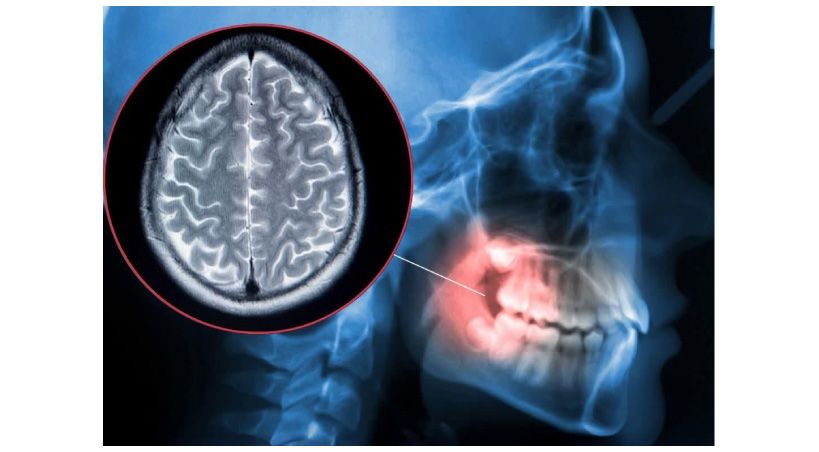

Dispositivos dentales y resistencia antimicrobiana

Desafíos, innovaciones y cumplimiento normativo